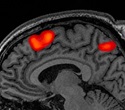

Our study measured frontal brain activity in the prefrontal cortex of healthy adults when they had contact with a dog compared with when they had contact with a plush animal. We measured brain activity with near-infrared spectroscopy. Participants had contact with the dog three times as well as three times with the plush animal. Next, they watched the animal (both the live and plush animal), felt it passively, then petted it actively. So, the interaction became closer, the stimulation rose, and more different senses were involved. We found that frontal brain activity increased when contact with the dog or a plush animal became closer. Our result confirms previous studies linking closer contact with animals or control stimuli with increased brain activation.

Image Credit: Rahel Marti & The University of BaselImage Credit: Rahel Marti & The University of Basel

Further, the participants had higher brain activity when interacting with a dog than when interacting with a plush animal. This result is in line with previous studies. They showed higher brain activation while interacting with a live animal (dog, rabbit, guinea pig, cat, horse) compared to several control conditions.